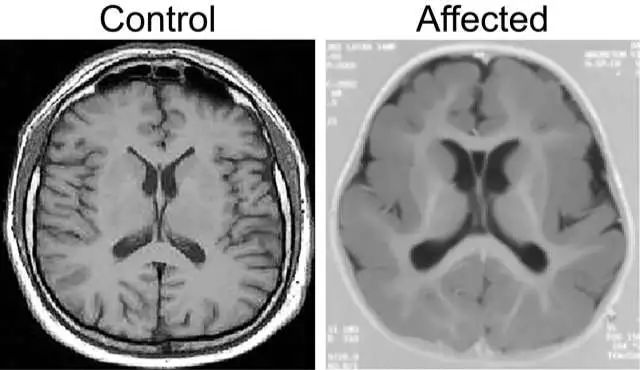

什么是巨脑回畸形

病例学习:平脑—巨脑回畸形

讨论 巨脑回畸形(pachygyria malformation)是一种先天性大脑发育